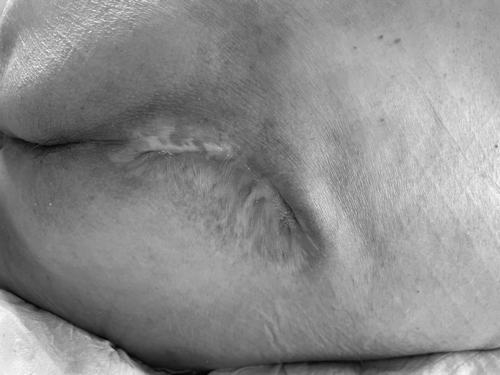

▲ 骶尾部

经过4个多月的精心护理和规范创面换药治疗,2位老人的压疮未行手术均痊愈,获得家属交口称赞。